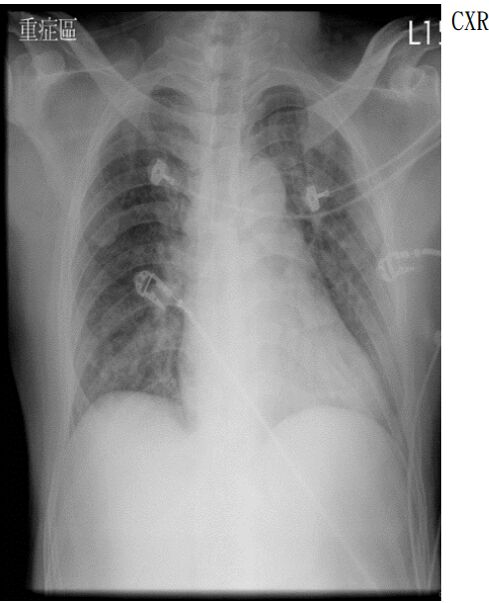

4. 病人是位29歲男性電子工程師派駐中國深圳,三個星期來,時有間歇性發燒及逐漸性呼吸困難,先在深圳 門診求醫,初以為一般感冒治療,後以支氣管炎診斷治療罔效,乃急回台灣求醫。經檢查,意識: E4M6V5; BP: 122/75 mmHg; PR: 116/min; RR: 21/min; Temperature: 37.6℃; SPO2: 94%(room air) 頸靜脈不怒張,未有貧血,胸部呈現瀰漫性濁音,心臟擴大,有Grade III/VI Diastolic murmurs at left upper sternal border,無肝脾腫大,無腹水。皮膚未有紅腫或出血斑點。2016/12/23心電圖及胸部X光如 圖。其血液、尿液及生化如次:Hemograms: WBC, 13.54(k/uL); RBC, 4.74(M/uL); Hb, 13.0 (gm%); HCT,40.2(%); MCV, 84.8 (fL); MCH,27.4(pg); Platelet,329 (k/uL); Seg, 81.5(%); Eos, 0.2(%)。尿檢: 正常。請 問這位年青病人的最可能診斷是: